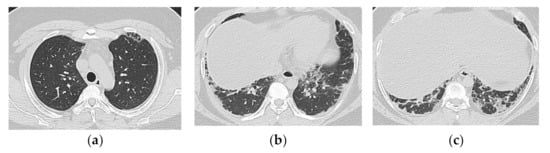

2.1. Subacute to Chronic Type

| Chronic to Subacute | Acute |

|---|---|

| Subacute course of disease > chronic | Acute or subacute onset, often with a rapid progressive course |

| Predominantly in the lower lobes of both lungs | Diffuse, or diffuse with a predominance of the lower lung zone |

| Peribronchovascular bundle distribution | Peribronchovascular distribution in the lower lobes, with parallel extension to the pleura |

| Reticular shadows and consolidation are common | GGO and consolidation |

| Reduced volume of the lower lobes | Basal volume loss |

| Traction bronchiectasis |